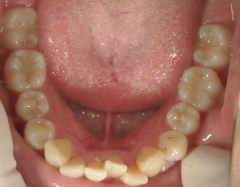

矯正歯科 治療前